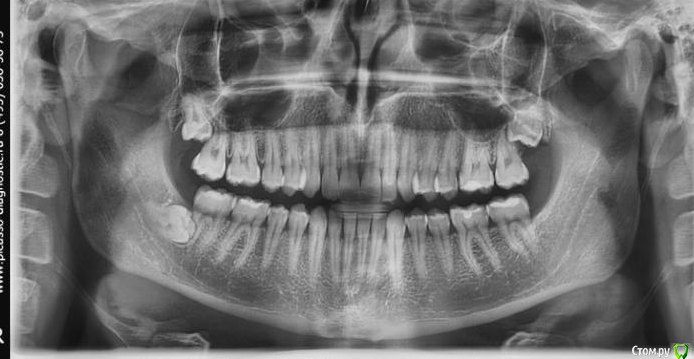

Начинающий хирург. Второй раз сталкиваюсь с такой вот 8ой (48), горизонтально и язычно лежащей. В первый раз удалял по протоколу, описанному Асанами и Касазаки в их учебнике "Квалифицированное удаление третьих моляров."

Хотел бы поинтересоваться у вас, как бы удалили вы?

Если не сложно, распишите поподробней, пожалуйста. Начиная от дизайна разреза, заканчивая ушиванием. Заранее спасибо всем!

Верхние 8ки буду удалять впервые. Если есть какие то особенности - буду рад если поделитесь опытом и советом!!!

Мое мнение: создать хороший доступ и визуальный контакт, аккуратно распилить его по шейке ( обратить внимание на прилегание н/л нерва) разделить и извлечь по частям!